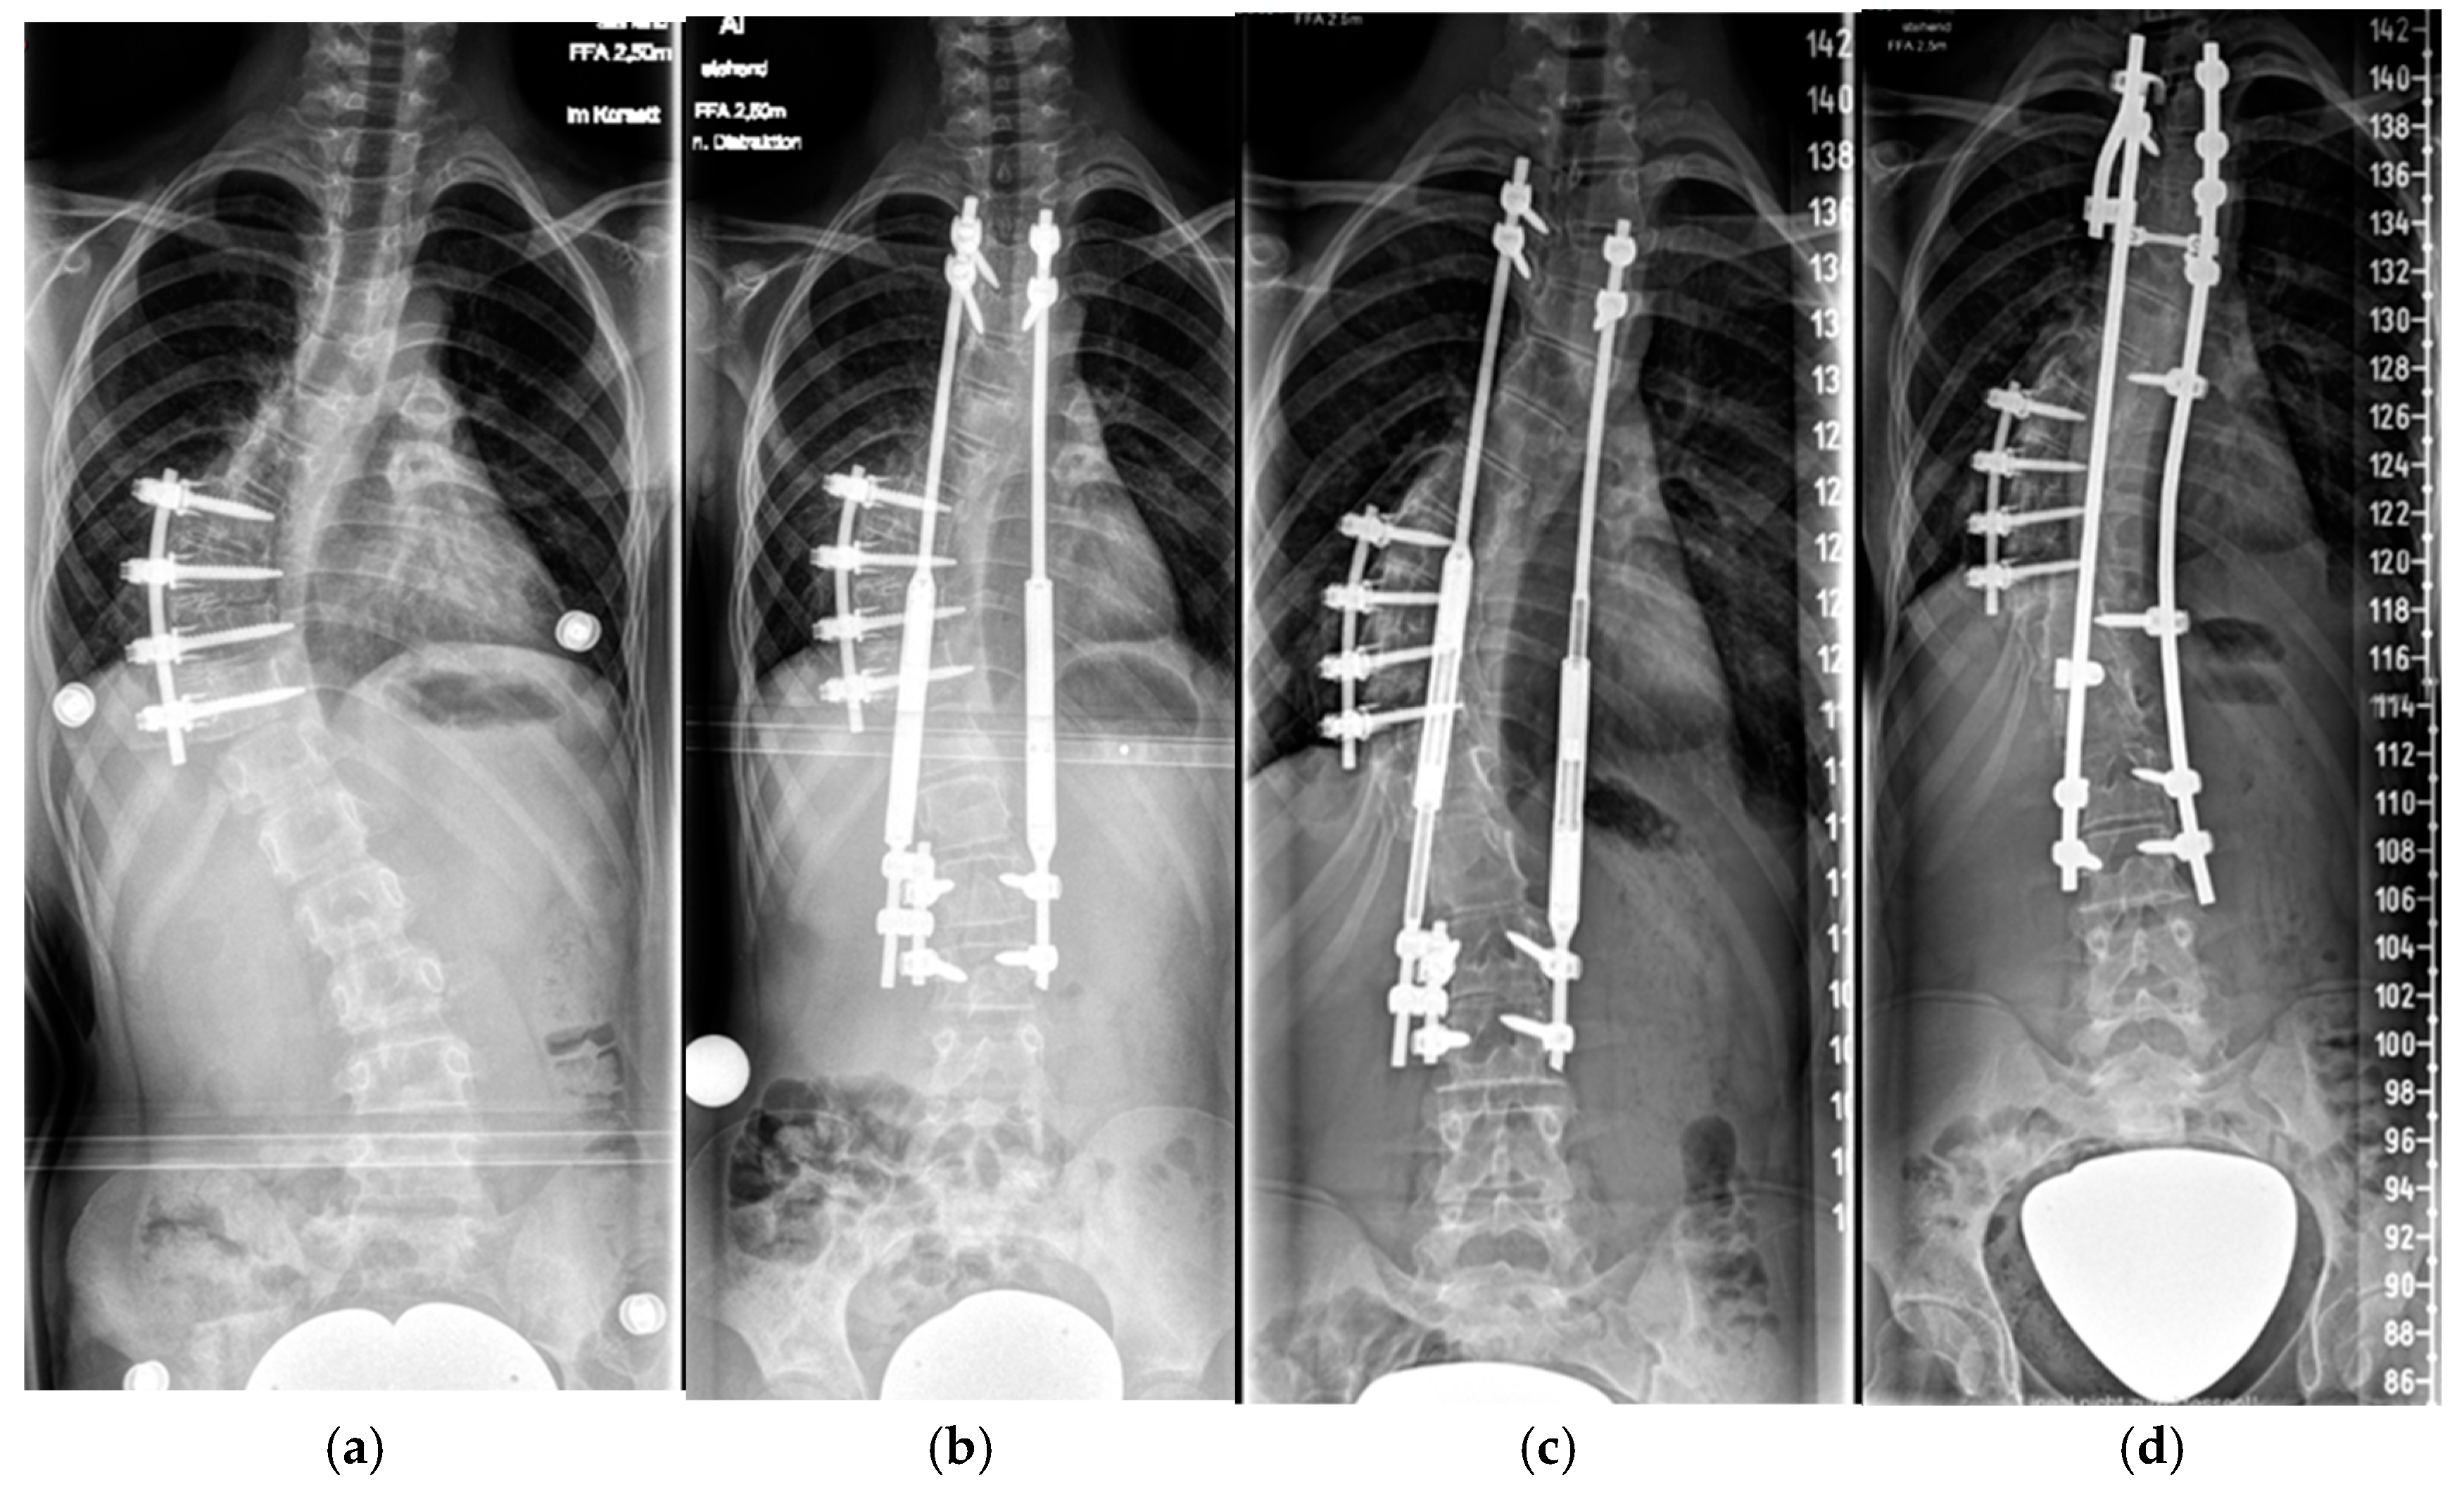

4.2.1. “Early Onset Spinal Deformity”

5.2.1. Growth-Preserving Techniques

| Type of Index Surgical Procedure | Age at Surgery * | Duration of Follow-Up * | Curve ° Pre-Op | Curve ° Last Follow-Up | % Curve Correction | T1-12 Postoperative † | T1-12 Last Follow-Up † | Growth T1-12 ‡ |

|---|---|---|---|---|---|---|---|---|

| Growth-preserving | 7.7 (±2.3) | 6.7 (±3.6) | 77 (±11.4) | 33.1 (±10.6) | 54.1 (±14.7) | 19.6 (±3) | 22.8 (±2.9) | 0.73 (±0.17) |

| Fusion | 13.4 (±2.3) | 3.1 (±1.7) | 66 (±13.6) | 26 (±11.3) | 66 (±23.7) |